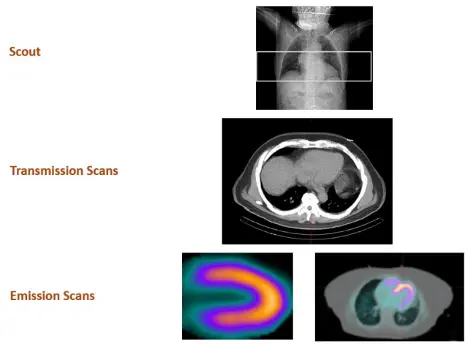

tl;dr: We collect transmission and perfusion images and superimpose them on one another. The CT and perfusion contours of the heart should be properly aligned (co-registration).

- Scout image to localize the heart

- Transmission scans – most commonly done with low-dose CT AC

- 📝 AC is a must for PET, but optional for SPECT

- 3 approaches to do AC, but everyone does CT-AC these days as it is very fast (patient motion is less of an issue), lower energy, and low noise/higher resolution

- Emission scans